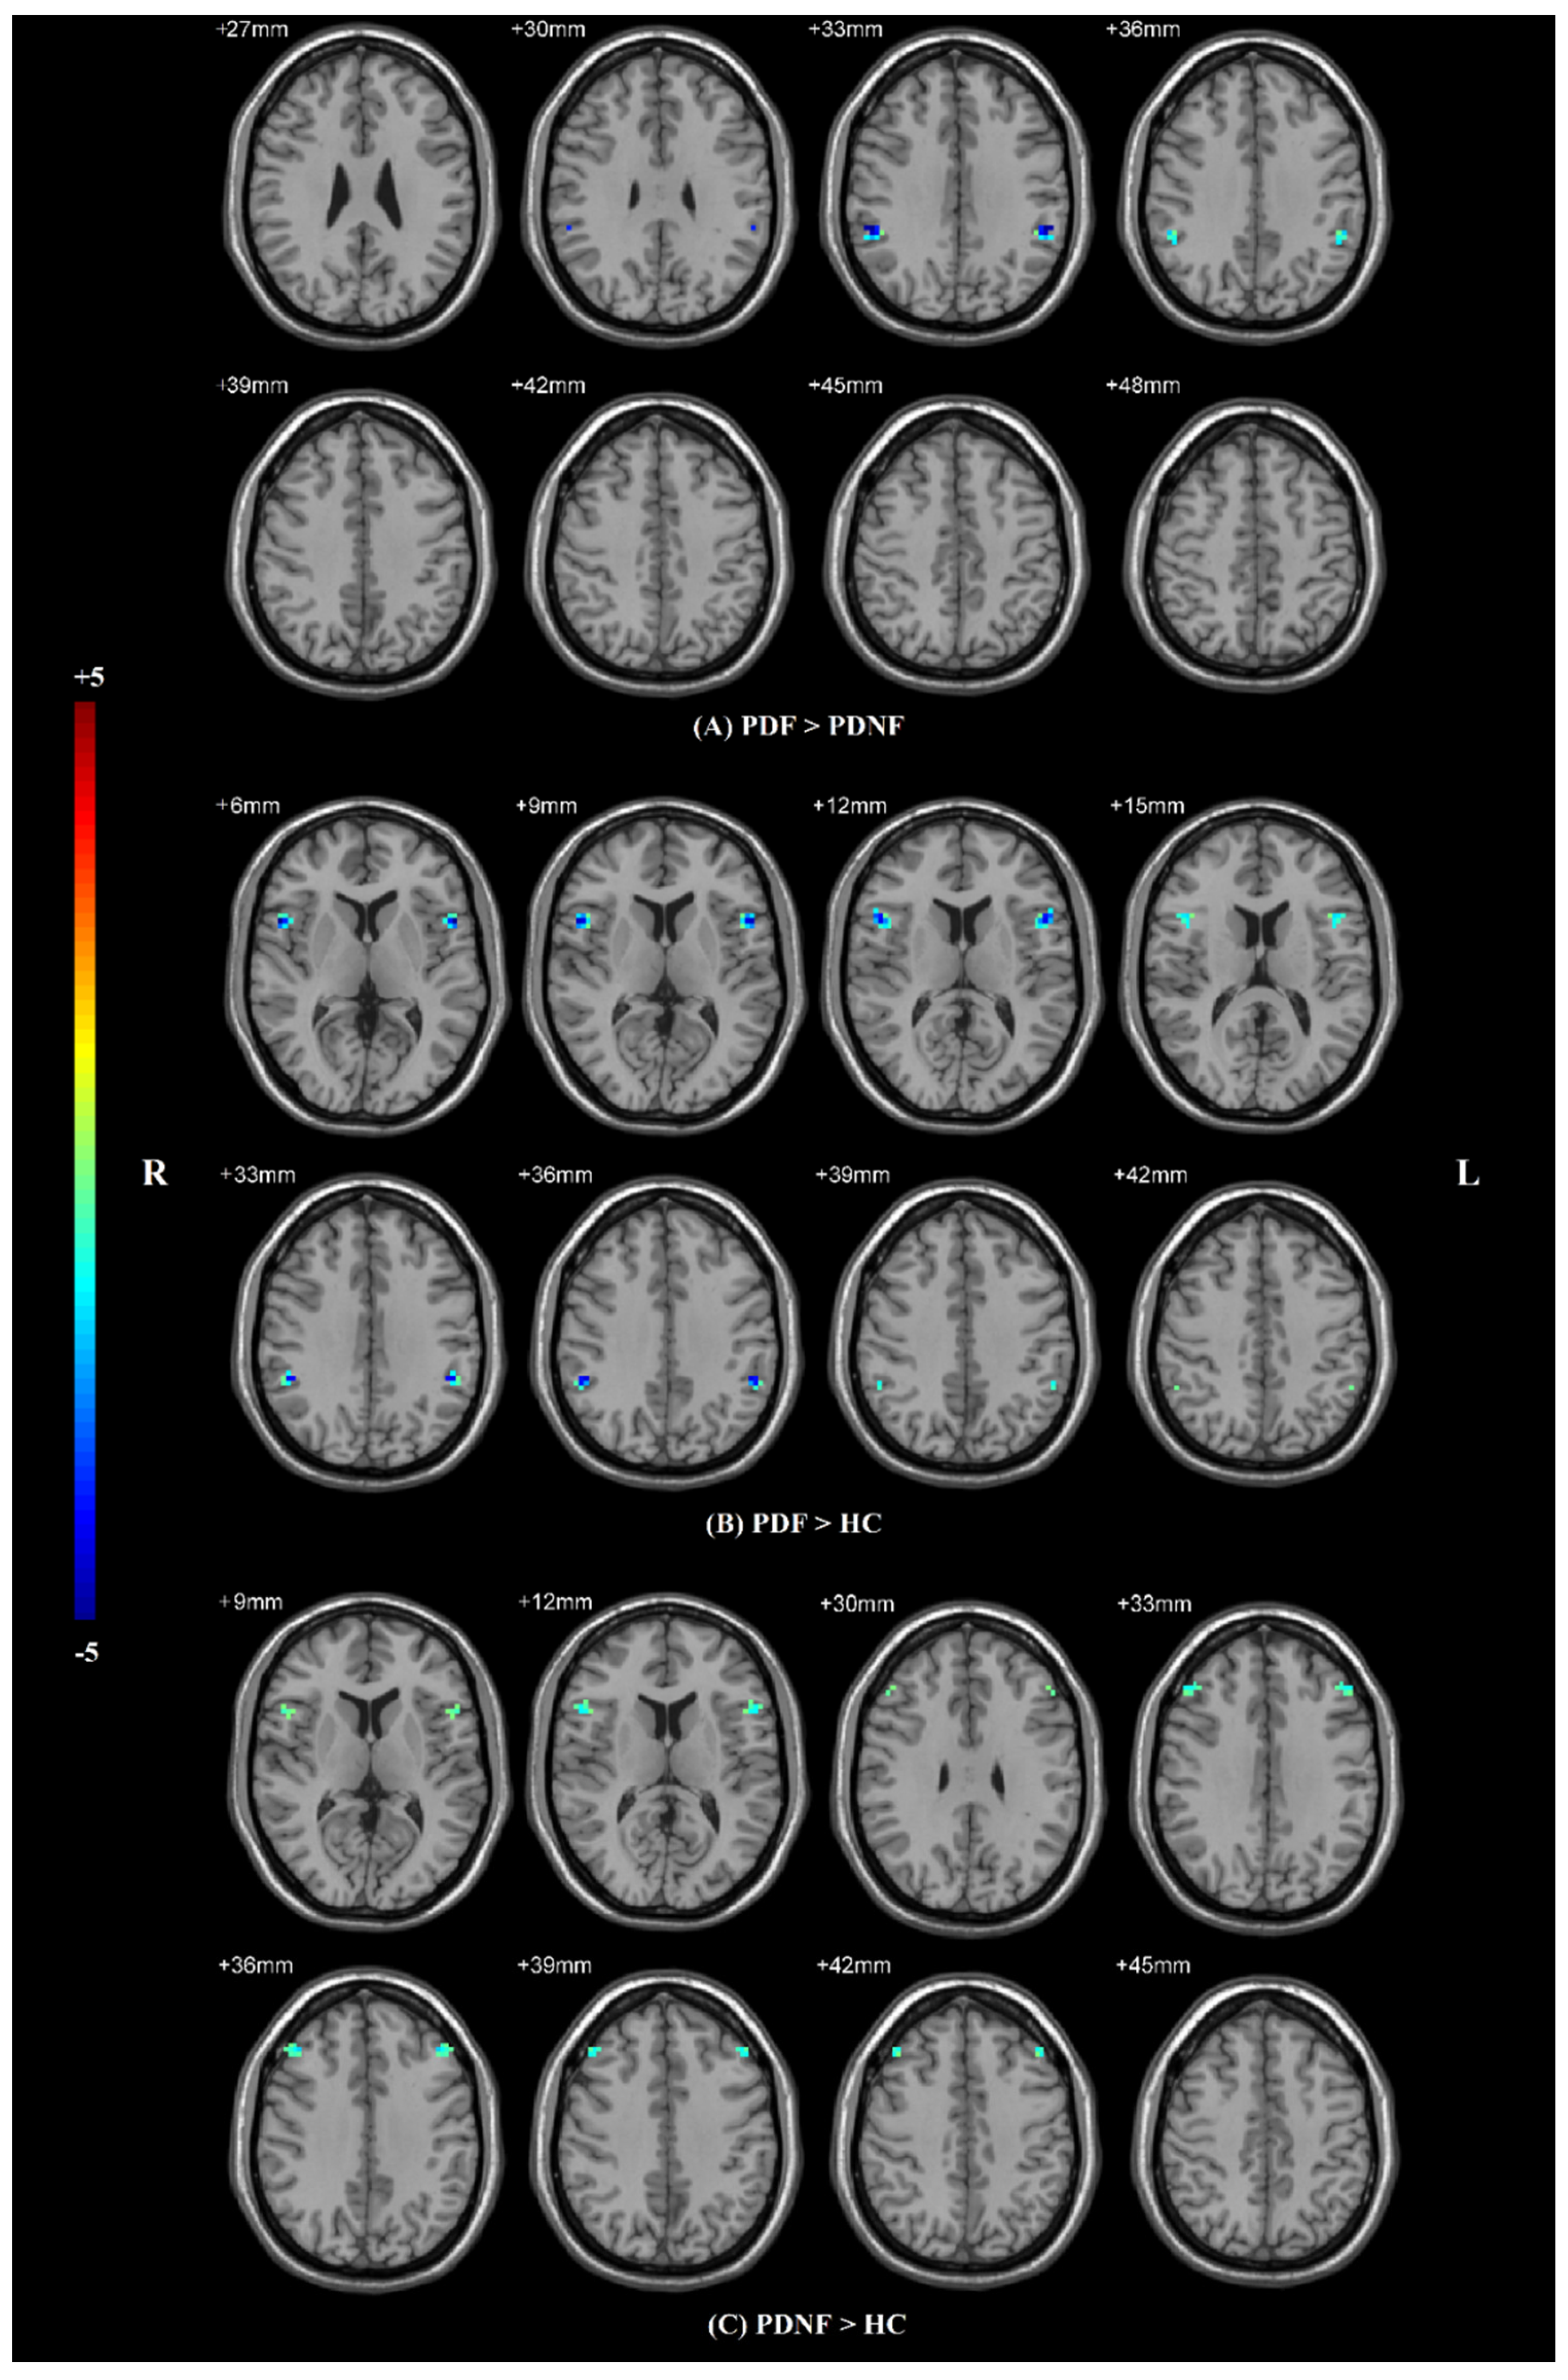

| Brain Regions (AAL) | Number of Voxels | MNI Coordinates | T Value | ||

|---|---|---|---|---|---|

| X | Y | Z | |||

| PDF > PDNF | |||||

| SMG | 15 | ±54 | −39 | 33 | −3.9081 |

| PDF > HCs | |||||

| IFG operc | 36 | ±54 | 12 | 6 | −4.7763 |

| SMG | 15 | ±51 | −42 | 36 | −4.4129 |

| PDNF > HCs | |||||

| IFG operc | 12 | ±54 | 15 | 12 | −3.6089 |

| MFG | 27 | ±42 | 33 | 36 | −3.8621 |